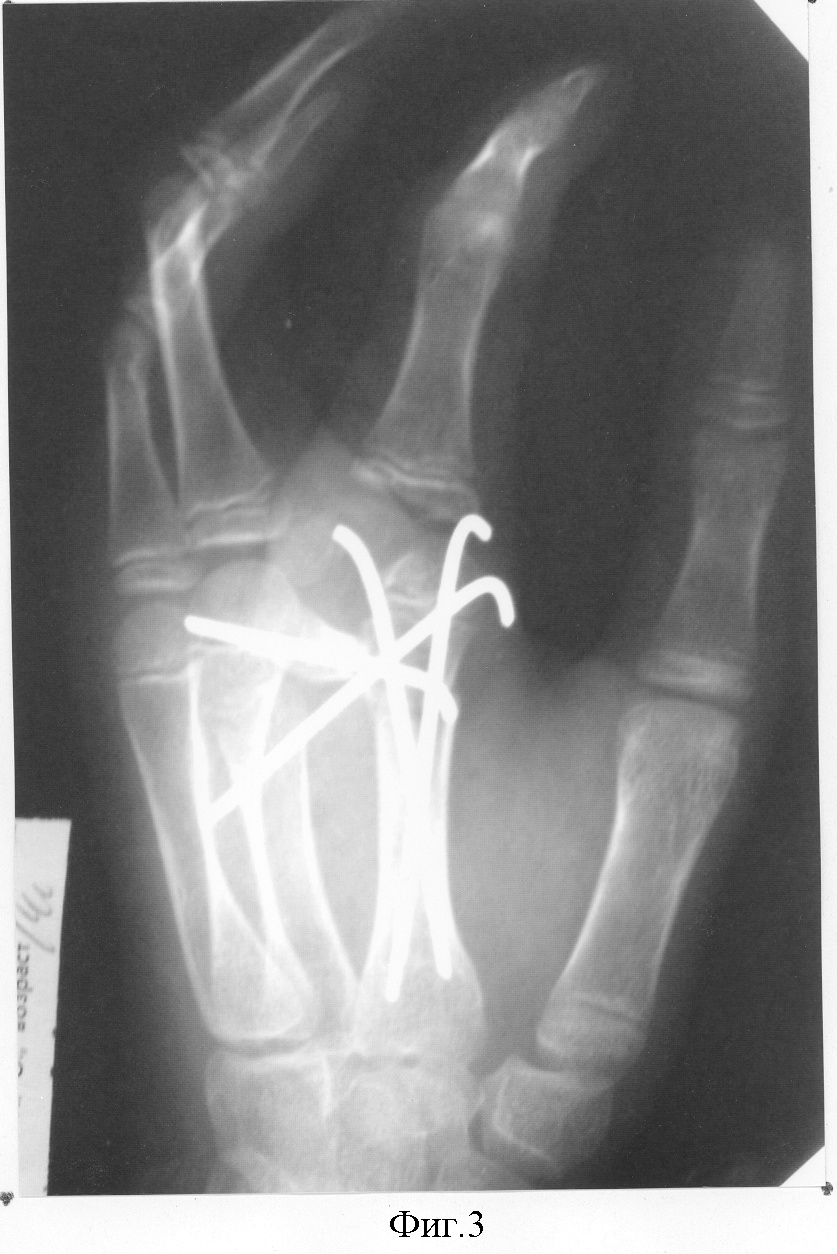

29.05.03 г. в отделении хирургии кисти НИЦТ «ВТО» выполнена операция по вышеописанной методике: ракетообразный разрез по расщелине кисти, с тыльного доступа вычленена головка дополнительной поперечной кости со второго пястно-фалангового сочленения, смещены навстречу друг другу вторая и третья пястные кости до достижения анатомической ширины кисти. Приложив дополнительную поперечную кость с тылу второй пястной кости, определена необходимая длина этой кости, подлежащая удалению. После этого удален лучевой конец дополнительной поперечной кости. Под головкой поперечно перепилена вторая пястная кость, и второй палец вместе с головкой пястной кости ротирован до функциональной позиции второго пальца по отношению к кисти. Достигнутое положение костей фиксировано спицами (фиг.3). Послойные швы на рану. Спиртовая повязка. Гипс до снятия кожных швов. Заживление раны первичным натяжением. Спицы удалены через 2 мес. Контрольный осмотр через 1,5 года. Достигнута хорошая анатомическая структура и улучшилась функция кисти (фиг.4,5).